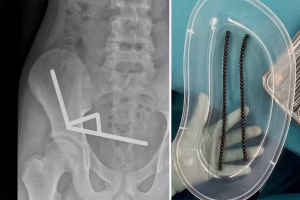

trending_flat Свет Момче (13) хоспитализирано откако проголтало десетици неодимиумски магнети – му е отстранет дел од цревата Lorita October 27, 2025